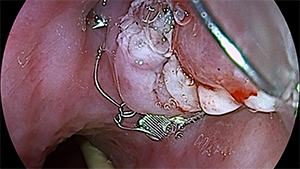

2024年4月7日,李大娘的治疗开始了。我们用氩离子凝固术破坏瘘口周围瘢痕组织,为黏膜愈合提供条件;然后用内镜吻合夹将瘘口处黏膜完全封闭;最后置入空肠营养管,保证黏膜愈合期间的营养需求。整个治疗过程快速、微创,几乎没有出现出血。